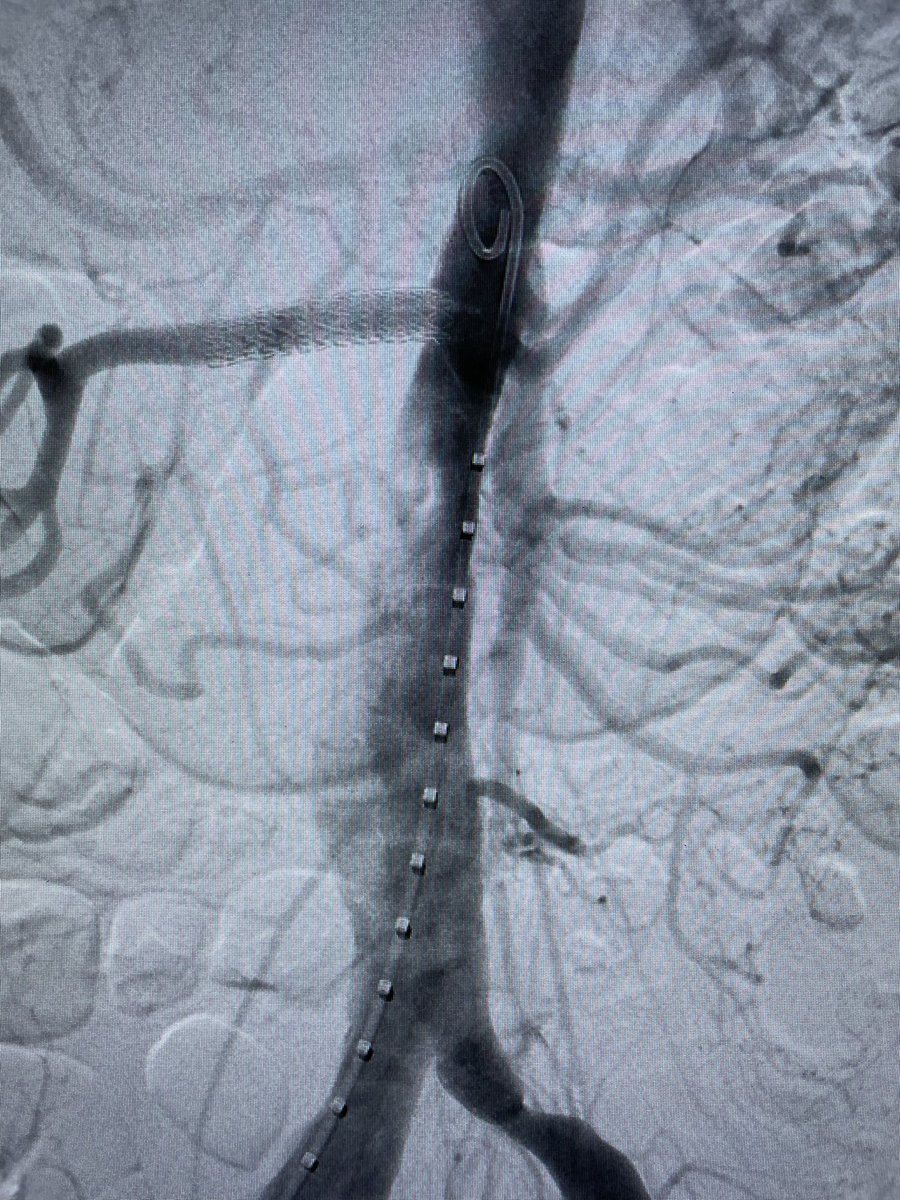

Patient with chronic mesenteric ischemia with unsuccessful endovascular attempt treated with aorta to SMA bypass (Dacron). Replaced common hepatic from SMA! Vascular Surgery Associates Cedars-Sinai Division of Vascular Surgery Department of Surgery at Cedars-Sinai #vascularsurgery #SoMe4Surgery #MedEd